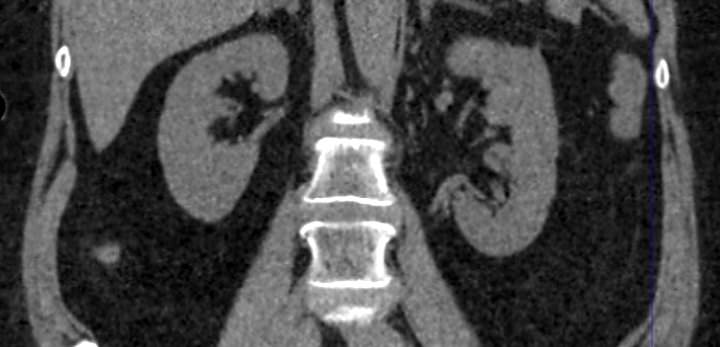

Что показывает КТ почек

Направить на процедуру КТ почек могут такие специалисты: врач-уролог, нефролог, онколог, терапевт или хирург. Исследование назначается с целью:

- визуализации почек и мочевыводящих путей, других прилегающих систем

- определение правильности положения почек и мочевого пузыря

- диагностика изменений в развитии, нарушения формы, размещения в забрюшинном пространстве почек, сращение, неправильное количество органов

- исследование на предмет камней в почках и сопутствующих им патологиям

- диагностика злокачественных, доброкачественных образований

- исследование надпочечников